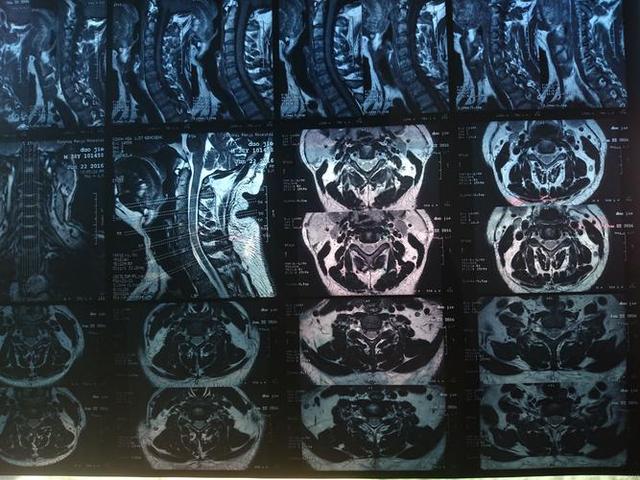

核磁共振成像(MRI)是一种高精度医学影像诊断技术,因其高分辨率和无辐射成像而备受青睐。然而,在使用核磁共振仪器时,必须避免将金属物质带入仪器内部。为什么金属不能带入核磁共振仪器?将金属管丢入仪器内会发生什么?

核磁共振成像是一种基于核磁共振原理的医学影像诊断技术。核磁共振技术从物理学角度探究了原子核在强磁场中的行为。核磁共振成像的原理基于核磁共振现象,利用磁共振信号的特征进行成像。在成像过程中,可以通过扫描和处理来获取人体内部器官、组织和血管的具体结构和病变情况。

金属物质在核磁共振成像中的作用是扰动磁场。由于金属的电导率比空气或水等非金属物质高得多,因此金属会在磁场中产生涡流,其电流会产生磁场,并且将磁场与样品组织区分开来。这会导致电流在金属表面产生高强度的磁场,扰动核磁共振成像磁场的均匀性和稳定性,从而影响成像质量。这就是为什么在核磁共振成像过程中金属物质必须被避免的主要原因。来源: www.ws46.com

当金属物质被带入核磁共振仪器中时,会出现较大的磁场扰动,导致成像效果受影响,出现伪影,使得MRI图像失真或不能使用。具体来说,金属管会扰乱仪器中的磁场,导致磁场不稳定,MRI图像质量下降。而且,金属在磁共振成像过程中还会产生热量,直接接触人体组织可能会导致组织损伤。